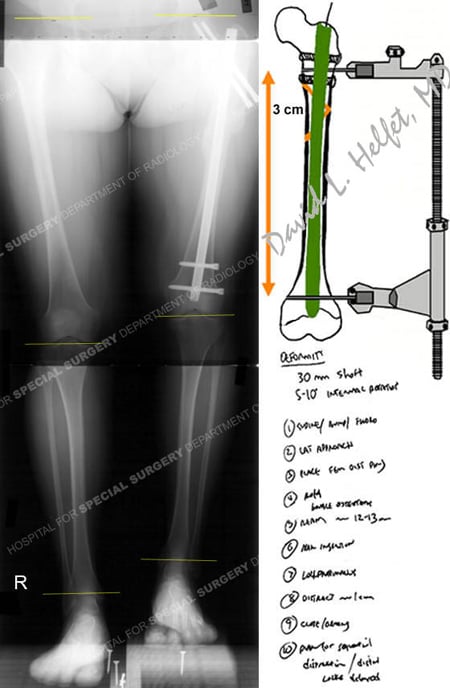

The Future of Intramedullary Limb Lengthening。Motorized Internal Limb Lengthening: An Updated Review。Lower limb lengthening over an intramedullary nail: a long。タイトル Intramedullary Limb Lengthening. Principles and Practice著者 Stuart A. Green Mark T. Dahl書き込み等なく綺麗な状態です。。